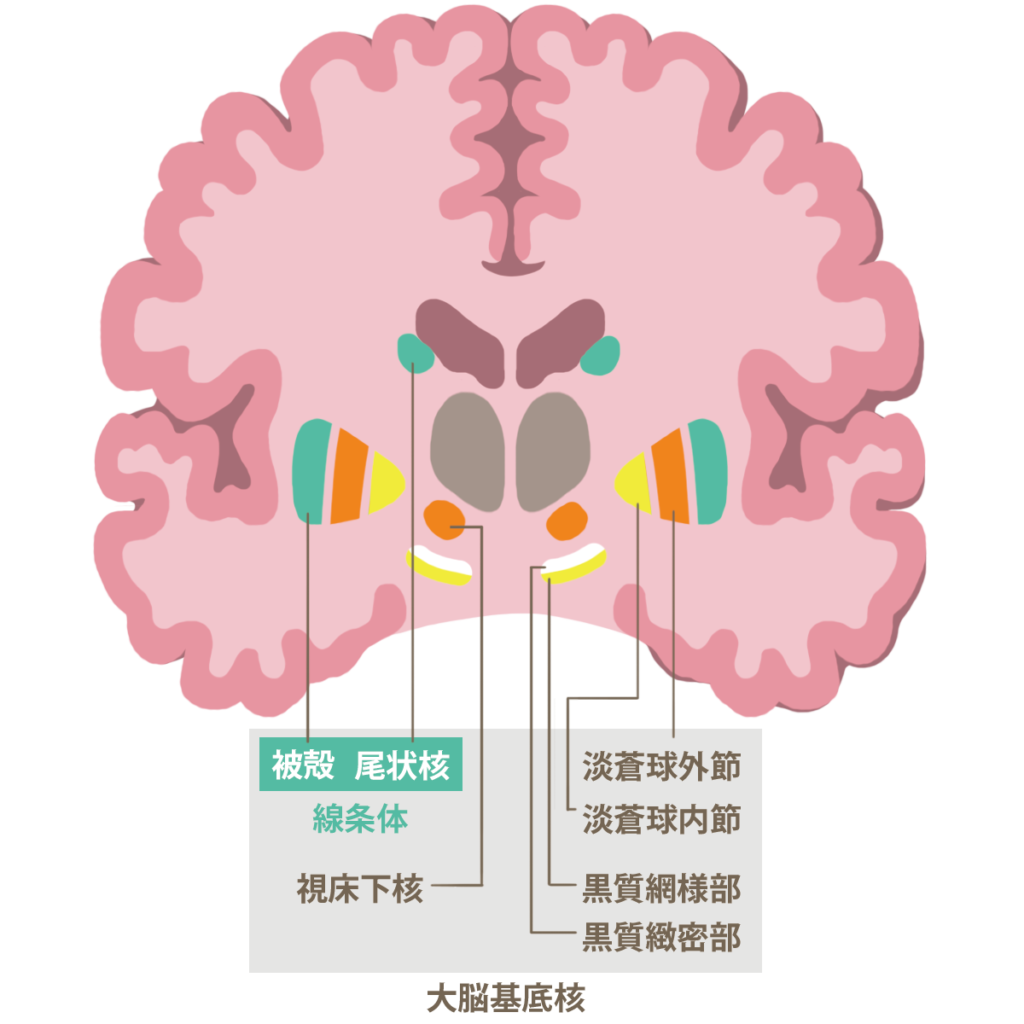

大脳皮質 辺縁系 基底核

ハンチントン病 09 脳 脊髄 末梢神経の病気 Msdマニュアル家庭版

間脳 中脳と大脳基底核 Sideswipe 医学 神経系 大脳

大脳皮質 辺縁系 基底核